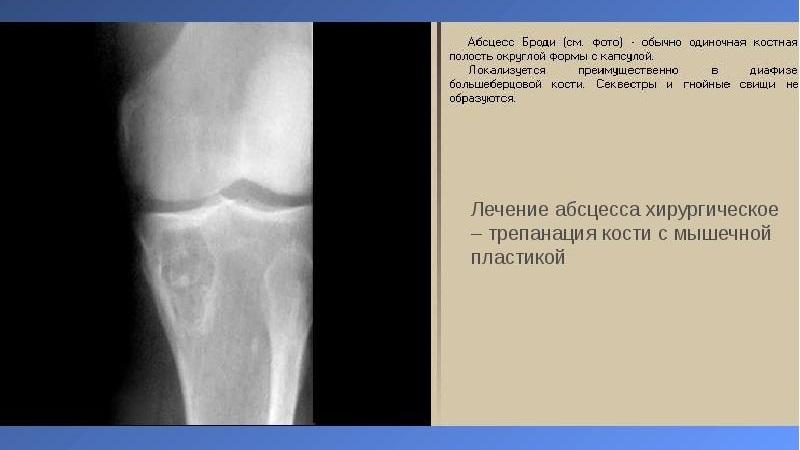

Отличительной чертой абсцесса Броди является наличие четкой изолированной полости без секвестра (участка омертвевшей ткани), имеющей правильную округлую форму. Это состояние можно диагностировать с помощью рентгенологического исследования.

Рентгенография и магнитно-резонансная томография – это единственные методы диагностики, которые позволяют полностью увидеть картину заболевания.

Окончательный диагноз устанавливается на основе четких данных рентгенографии.

Хирургическое вмешательство

Операция при абсцессе Броди рекомендуется в случае, если консервативные методы лечения не дают результатов. В ходе процедуры выполняется трепанация полости, после чего осуществляется выскабливание внутренней стенки. Рана закрывается наглухо. Часть костной ткани заменяется имплантатом. При наличии крупных полостей может быть использована мышечная пластика.